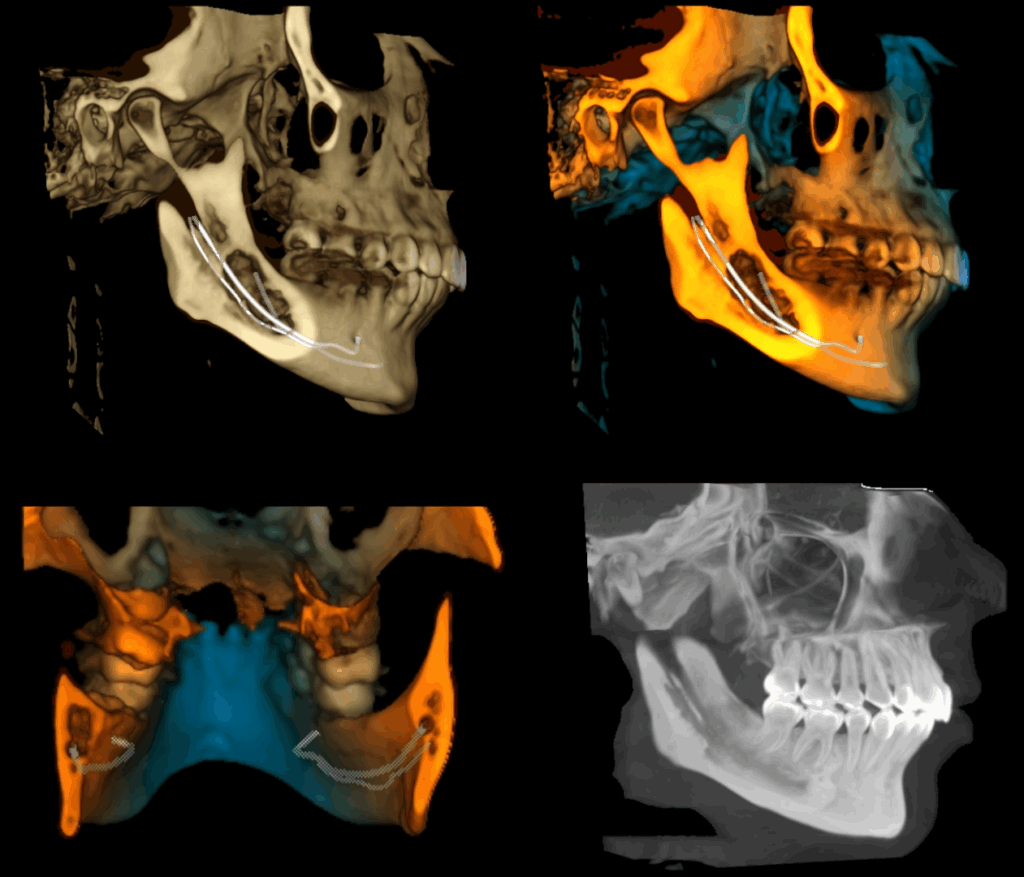

A la evaluación de la tomografía de cráneo completo se encontró un hallazgo imagenológico en el cuarto cuadrante, se observó la bifurcación del conducto dentario inferior que iba desde su entrada por el agujero mandibular y se orienta caudal al conducto dentario principal para volver a unirse con el mismo a nivel apical de la primera molar.

RECONSTRUCCIÓN 3D

CONCLUSIÓN

Bifurcación del conducto dentario inferior unilateral.